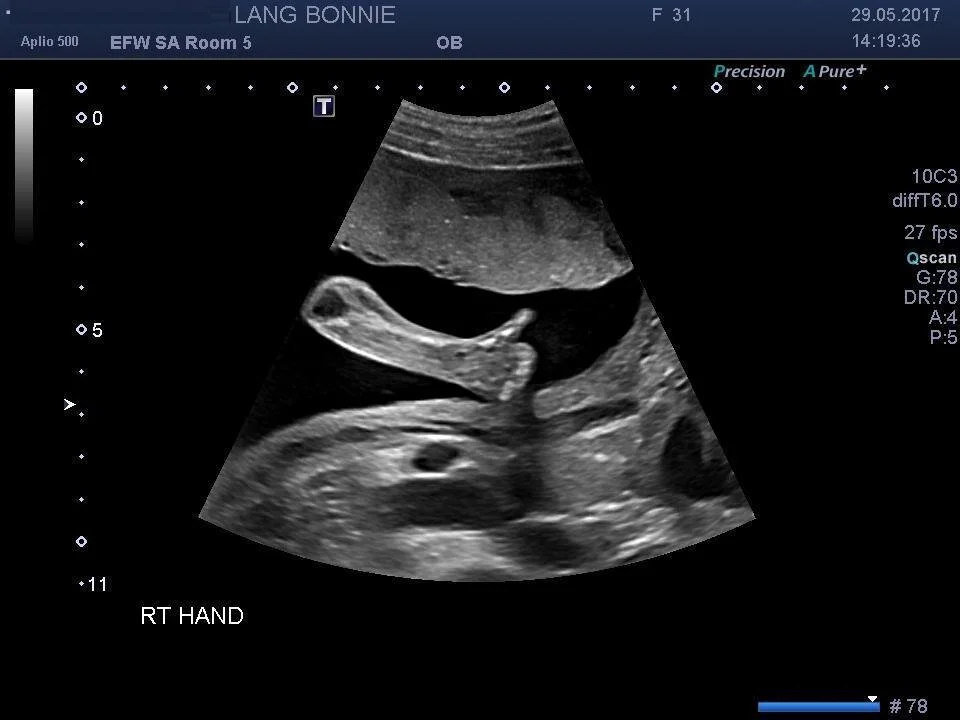

I mean, that babe is really growing! Sometimes I look down at my expanding belly and think, “Is there REALLY something in there that’s progressing and full of life?” – it’s still hard to believe this is our reality and daily we are grateful for this little guy (or girl – we aren’t finding out!). The ultrasound showed us the babe’s cerebellum, spine, fingers and toes, four chambers of her beating heart, and a very clear thumbs up. Love it!

Thumbs up, mom!